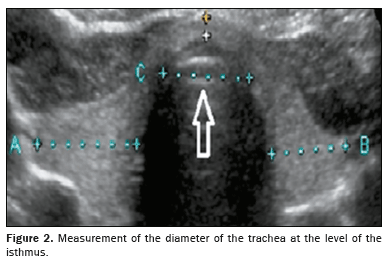

Quantitative data were extracted from archived thyroid ultrasound images. Standardized measurements included the MTLD, calculated as the average of the transverse and anteroposterior diameters of the largest lobe, as shown in Figure 1, and the TTD, the measurement of which was standardized to be performed in the transverse plane at the level of the thyroid isthmus, as illustrated in Figure 2. Despite the isthmus presenting anatomical variations, including a filiform appearance in some cases, the adopted protocol ensured image acquisition in the same anatomical plane, ensuring comparability and consistency of measurements among the cases evaluated. In addition, as depicted in Figure 3, thyroid volume was calculated directly from sonograms by using the ellipsoid formula: length × width × depth × correction factor (0.470). We also calculated the tracheal index, which is defined as the ratio between the sum of the widths of the thyroid lobes and the width of the trachea.